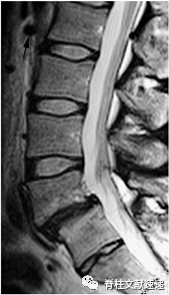

有学者提出,右肾动脉(RRA)的位置可用于在矢状位MRI上识别腰椎节段,因为RRA通常位于L1/2椎间盘附近(如图5),但由于有时动脉不能被识别等问题,这一标准在大约25%的患者中不适用。

图5注:矢状位T2加权像MRI结果显示右肾动脉(黑色箭头处),使用这种方法将最近的椎间盘标记为L1/2,移行椎标记为L5。